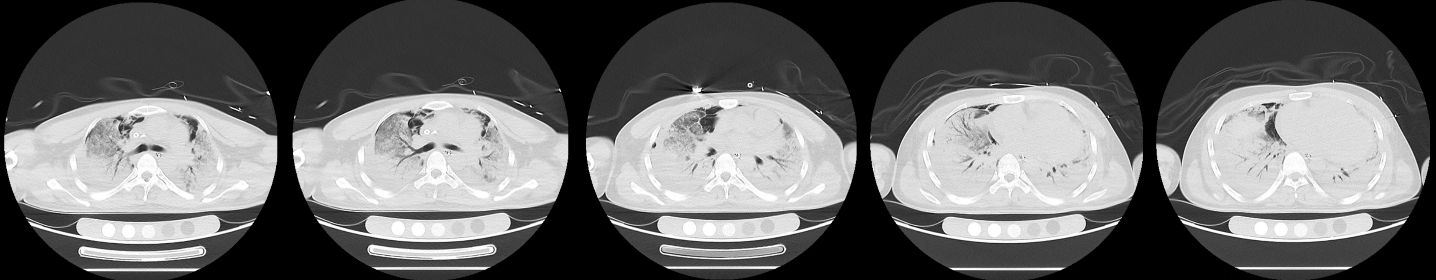

1 病例资料2024-11-15,某工地操作间有值班人员3人,分别为上铺(距地面1.8 m)A某,下铺(距地面0.4 m)B某、C某,事发当天为午休时间,设备出现故障,下午14时维修人员D某进入操作间维修,并将门窗打开,完成维修操作;事发后24 h内4名患者均出现不同程度的恶心、呕吐等消化道症状,起初考虑可能与食物中毒有关,前往当地医院就诊,完善血便常规、胸腹CT等相关检查未见明显异常,在医院给予吸氧补液静卧留观,留观期间4人先后出现不同程度的咽痛、咳嗽、胸闷、憋气等不适,吸氧不能缓解,再次行胸部CT检查示双肺弥漫性改变,间质改变可能,考虑为吸入有毒有害气体,后经采样检测操作间气体残留为全氟-4-甲基-2戊稀[Perfluoro(4-methylpent-2-ene),D1](D1纯度99.92%),导致急性呼吸窘迫综合症(acute respiratory distress syndrome, ARDS)。参照2002年职业性急性有机氟中毒诊断标准[1],A某诊断为急性中度有机氟气体中毒,B某、C某、D某诊断为急性重度有机氟气体中毒(PaO2/FiO2 < 100 mmHg,1 mmHg=0.098 kPa)。立即给予大剂量(120 mg)甲泼尼龙琥珀酸钠治疗,同时补充多种微量元素,加用甲钴胺、硫辛酸,钙剂解毒,后续加用特殊解毒剂乙酰胺治疗。治疗1周后,上铺的A某胸闷、憋气症状较前好转,影像未见明显进展,但患者仍遗留有间断气短症状;其余人员病情持续恶化,出现呼吸衰竭,转入重症医学科,给予气管插管接呼吸机辅助通气,维修人员D某上呼吸机后能基本维持,但不能脱机,继续观察患者病情变化;而下铺患者B某、C某症状不断加重,即使给予呼吸机治疗低氧状态仍未见明显改善,于2024-11-29转入本院进一步治疗。B某、C某入本院时查体:双肺叩诊呈清音,双肺呼吸音粗,可闻及干湿性啰音,具体指标见表 1,图 1、2为肺部影像进展情况。入院给予镇静镇痛、机械通气及抗感染、抗炎、抑酸等治疗,呼吸困难仍持续加重,存在难以纠正的低氧血症及高碳酸血症,表现为ARDS,有体外膜肺氧合(extracorporeal membrane oxygenation, ECMO)治疗指征,参考国内外相关救治经验[2-6],给予患者静脉-静脉ECMO(veno-venous extracorporeal membrane oxygenation, V-V ECMO)治疗,具体参数见表 2。

| 图 2 C某发病第1、3、10天胸部CT |